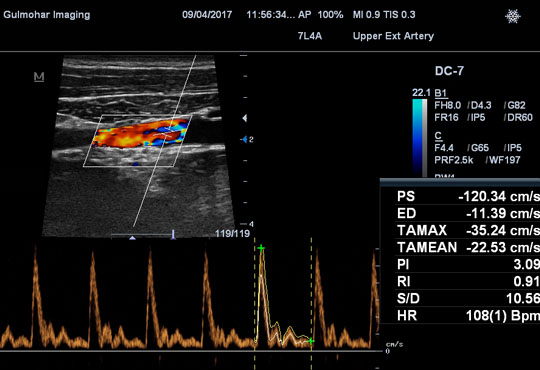

Renal Doppler is intended to perceive direct or indirect evidence of Renal Arterial stenosis (narrowing of artery supplying kidneys) in patients with Hypertension (High blood pressure) Portal Venous Doppler can diagnose severity of Cirrhosis of Liver.